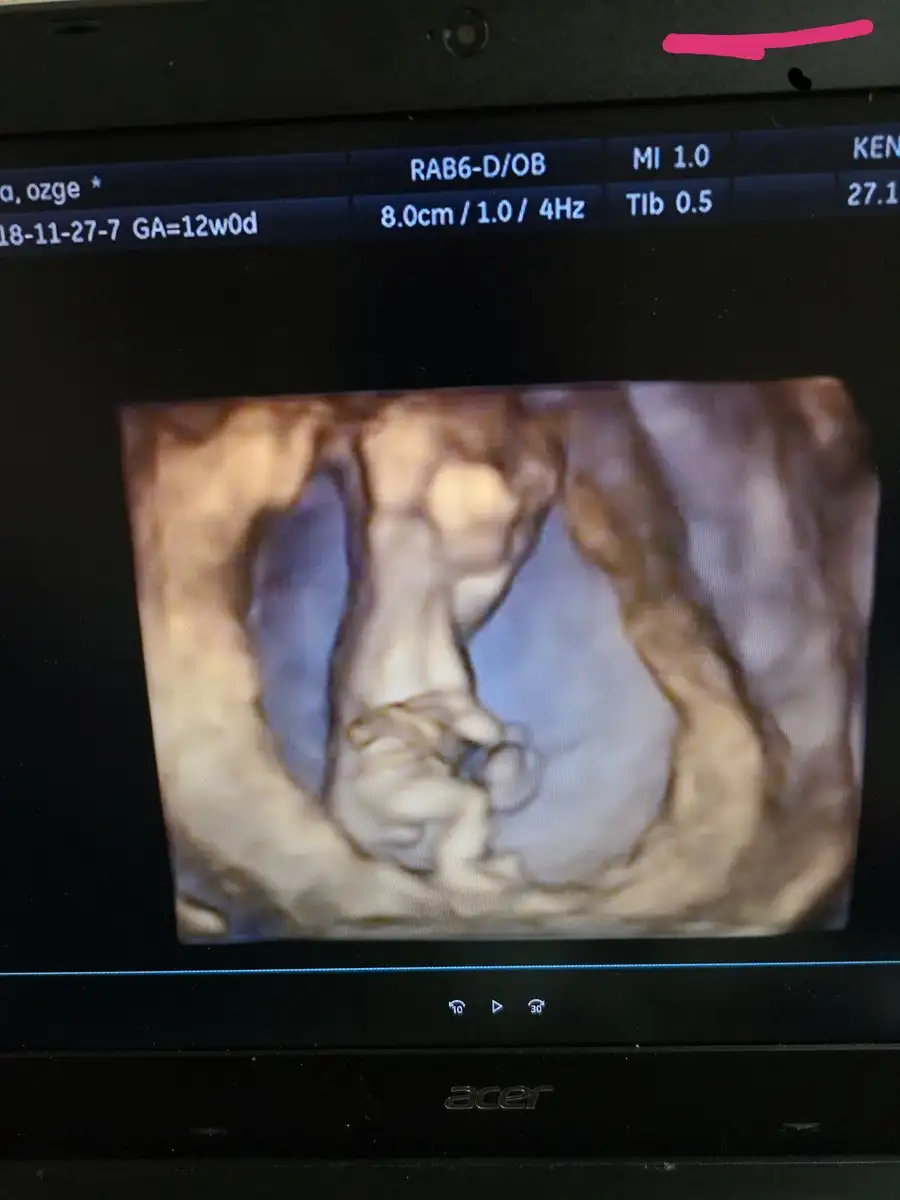

IMG_20181127_173008.webp